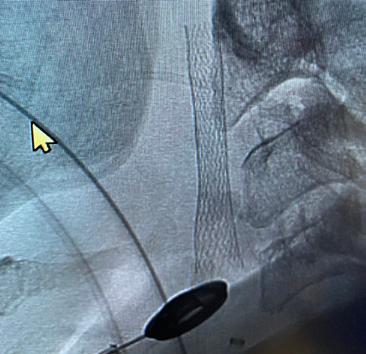

For patients with severe carotid disease, there are different procedures to reduce the risk of a stroke. In carotid endarterectomy, the provider will make a two-inch neck incision to expose the carotid artery. First, the artery is temporarily clamped to prevent bleeding. Then, the artery is opened and cleaned to completely remove the plaque. Finally, the artery is sewn, and the incision is closed.

In carotid artery stenting, a small tube or catheter is inserted through the wrist or the leg and steered within the body’s vessels to the carotid artery. First, a protection device is positioned to catch any debris that may become dislodged. Then, a metallic tube called a stent is expanded to push the plaque to the side and widen the artery. Finally, the machinery is removed, and the entry sites are closed.